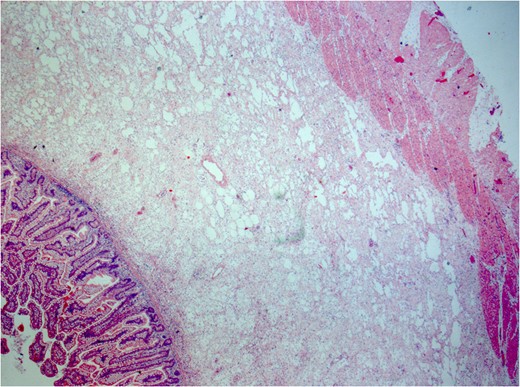

Histology: small bowel histology showing margin of resection with prominent submucosa oedema and mild inflammation.